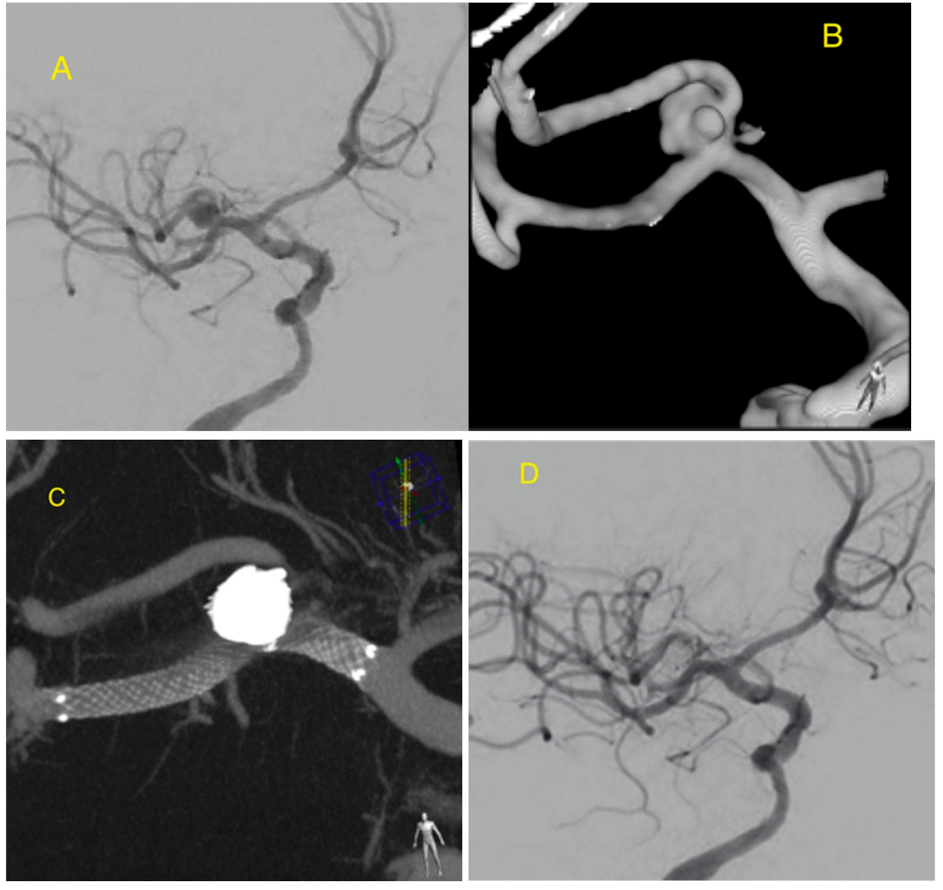

Initial Experience with LVIS EVO Stents for the Treatment of Intracranial Aneurysms

- Sirakov, A.; Bhogal, P.; Möhlenbruch, M.; Sirakov, S.S. Endovascular treatment of patients with intracranial aneurysms: Feasibility and successful employment of a new low profile visible intraluminal support (LVIS) EVO stent. Neuroradiol. J. 2020, 33, 377–385. [Google Scholar] [CrossRef]